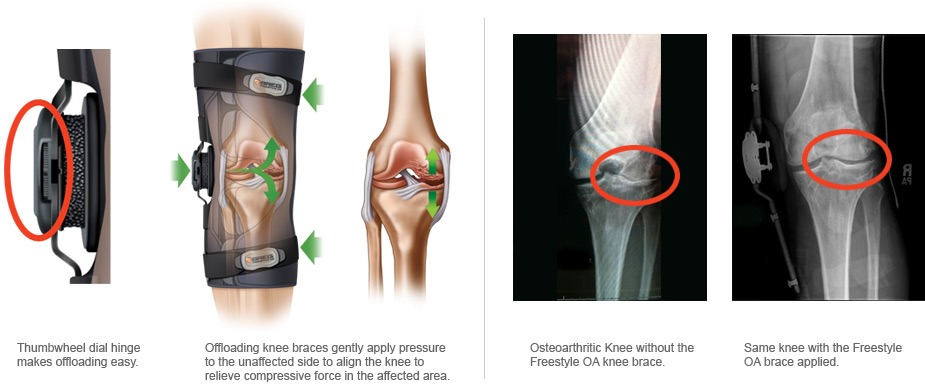

The Freestyle OA knee brace is designed with precision and patient comfort in mind. It’s a low-profile brace that provides focused compression around the knee joint, coupled with an innovative offloading mechanism. This mechanism is the heart of the brace’s effectiveness, specifically targeting the medial or lateral compartment of the knee, depending on the patient’s needs.

The offloading feature works by applying a gentle force that realigns the knee, shifting the weight away from the damaged part of the joint. This redistribution of weight relieves pressure on the affected area, reducing pain and improving mobility. The Freestyle OA brace achieves this through its unique thumbwheel dial hinge mechanism, allowing for precision adjustments without the need for additional tools.

- Customizable Support: The thumbwheel dial allows for easy adjustments, ensuring that each user can find the perfect level of support and comfort.